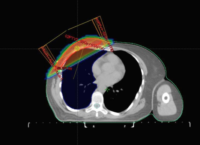

Volúmenes Blancoen Radioterapia conformada 3D Se puede definir la radioterapia conformada 3D como una técnica de